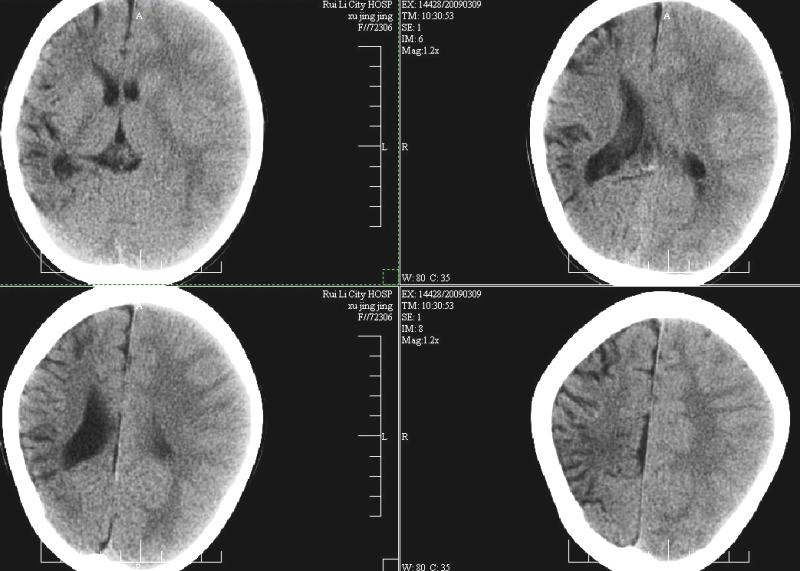

标题: PED1810:F,9岁。头痛,昏倒,一周一次,共半年。 [打印本页]

标题: PED1810:F,9岁。头痛,昏倒,一周一次,共半年。

ct:右顶叶脑软化灶合并右侧大脑半球发育不良可能。

右侧大脑半球脑萎缩。

中线平移,象发育不良